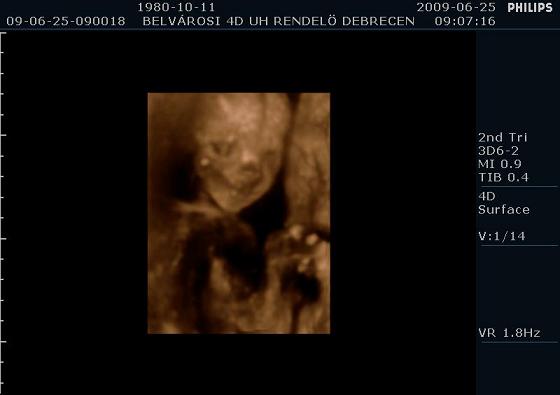

Mintha mosolyogna

Mintha mosolyogna